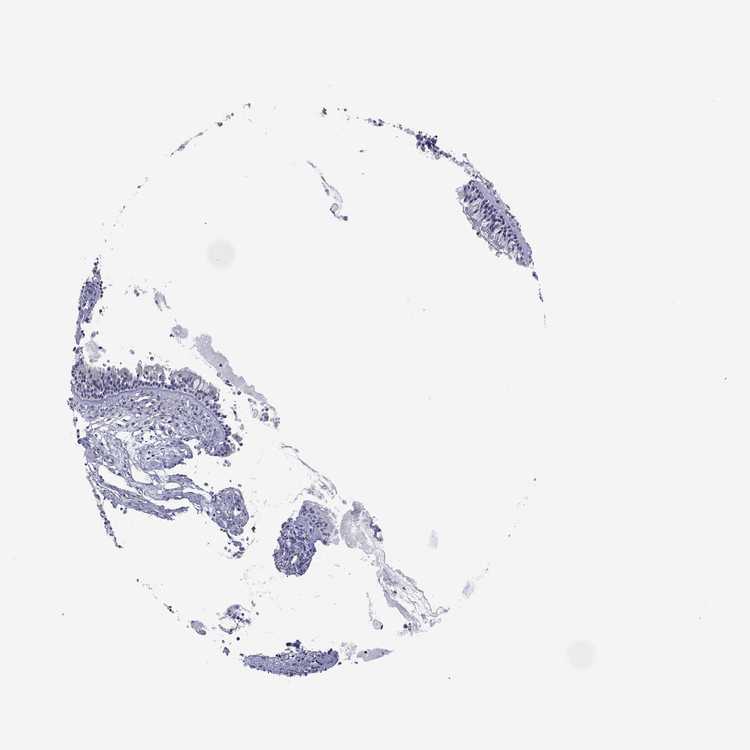

TISSUE PRIMARY DATA NASOPHARYNX Show tissue menu

NASOPHARYNX - Antibody stainingi

Antibody staining in the annotated cell types in the current human tissue is reported as not detected, low, medium, or high, based on conventional immunohistochemistry profiling in selected tissues. This score is based on the combination of the staining intensity and fraction of stained cells.

Each image is clickable and will lead to virtual microscopy that enables deeper exploration of all samples and also displays staining intensity scores, fraction scores and subcellular localization as well as patient and tissue information for each sample.

Antibody HPA003548Antibody CAB017633

Respiratory epithelial cells Not detectedNot detected